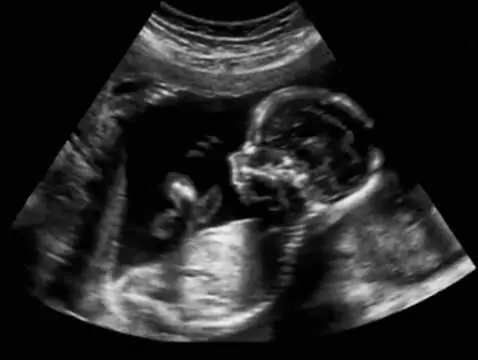

Find out what it is, when it should be performed and what information we can expect from a Medical US midterm scan in this article.

Prenatal tests have long played an important role in gynaecology and obstetrics, but nowadays their value is constantly increasing due to the fact that more and more women are becoming pregnant late....